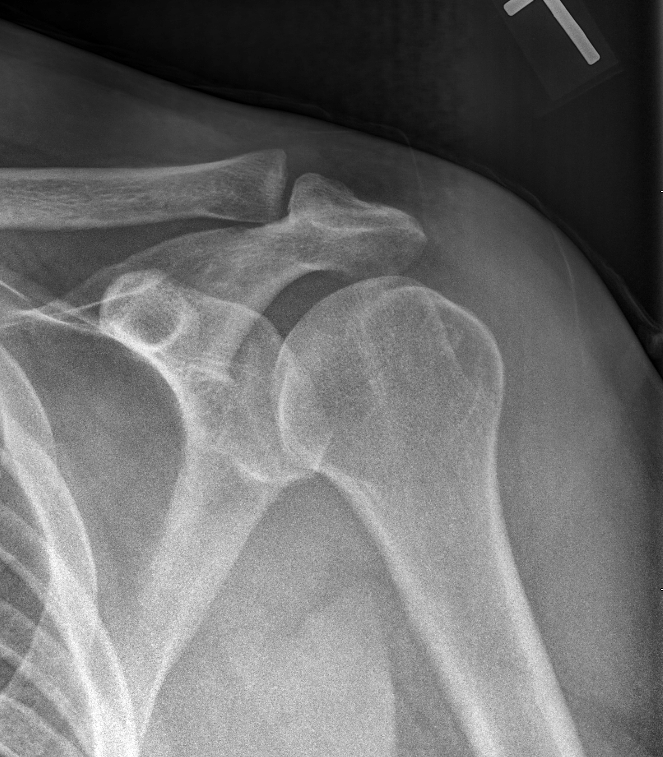

A 21-year-old man presents with shoulder pain after falling off his bike. What is your diagnosis?

Explanation: ***Acromioclavicular dislocation*** - **Fall on shoulder** mechanism commonly causes **AC joint injury** with **widened AC joint space** and **elevated distal clavicle** on X-ray - Clinical **piano key sign** (depressible distal clavicle) and **point tenderness** over AC joint are characteristic findings *Anterior glenohumeral joint dislocation* - Would show **humeral head displacement** anteriorly with loss of normal **glenohumeral joint relationship** on X-ray - Associated with **axillary nerve injury** and **Bankart lesions**, not consistent with AC joint pathology shown *Posterior glenohumeral dislocation* - Rare injury showing **lightbulb sign** on AP X-ray with **fixed internal rotation** of humerus - Often missed but would demonstrate **glenohumeral joint abnormality**, not isolated AC joint changes *All of the above* - Only **one specific diagnosis** can be made based on the radiographic evidence of AC joint pathology - **Multiple simultaneous dislocations** are extremely rare and not supported by typical imaging findings